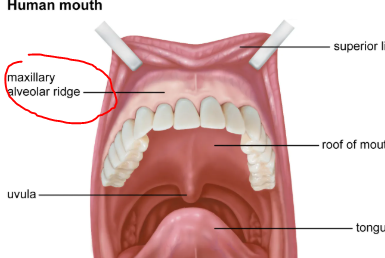

I had upper lip tie removal but my gums are like only 2mm in height

I had upper lip tie removal but my gums are like only 2mm in height